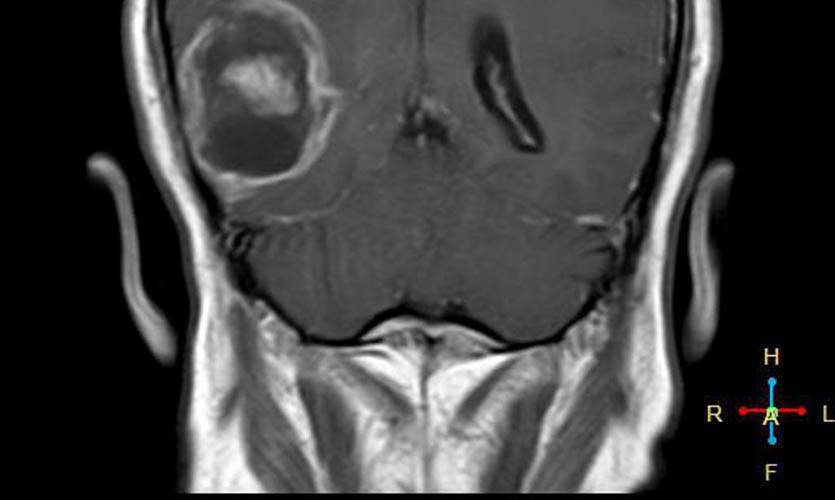

Было проведено исследование радиочастотных электромагнитных полей путём оценки общей кумулятивной дозы удельной энергии (TCSE) для каждого человека. Для каждого случая местоположение опухоли определяли нейрорадиологами, а центр опухоли оценивался компьютерным алгоритмом или непосредственно нейрорадиологом.

Для каждого случая средняя точка опухоли на трехмерной сетке определялась на основе радиологических изображений.

По итогам исследования выяснялось, что у пользователей мобильных телефонов наблюдалось повышение шансов появления злокачественных опухолей головного мозга и развития астроцитомы при использовании мобильных телефонов только с одной стороны головы.

Проще говоря, если ваш смартфон лежит ночью с правой стороны (по статистике именно так), то риск появления опухоли возрастает именно справа.